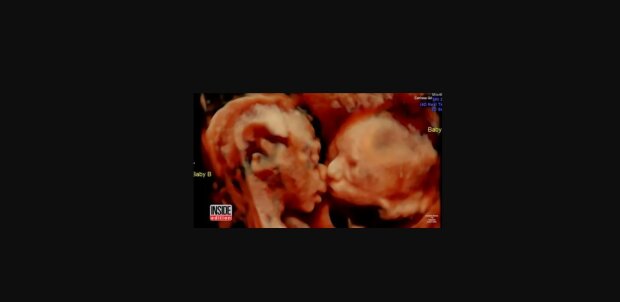

Carissa Rill i jej partner długo starali się o dziecko. Wiadomość o ciąży była więc spełnieniem ich marzeń. Nie przeraziła ich nawet wiadomość o tym, że na świecie pojawią się bliźnięta. Każde badanie USG było dla nich wielkim przeżyciem i możliwością spotkania z upragnionym potomkiem.

Podczas badania lekarz potwierdził, że ciąża. się prawidłowo, a przyszli rodzice nie mają powodów do obaw. W pewnym momencie jednak zachowanie dziecka zszokowało wszystkich.

Jak podaje portal "Goniec", dzieci ustawiy się przodem do kamery i zaczęło stykac sie ustami, co przypominało dawanie buziaka. Ten widok wzruszył przyszłych rodziców.